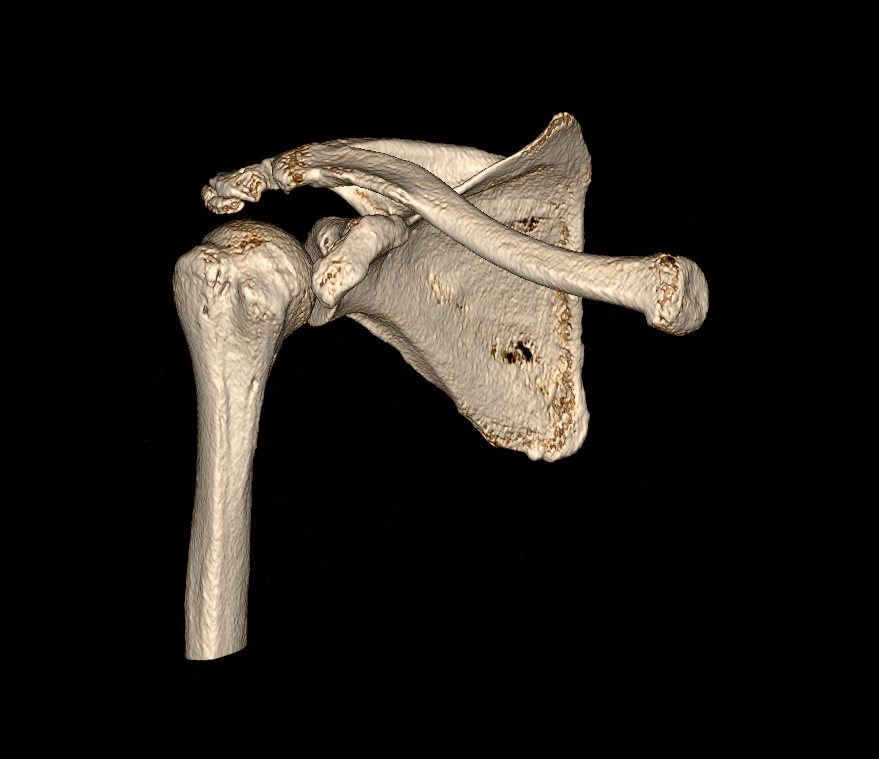

A tomografia computadorizada articular é um exame de diagnóstico por imagem de alta qualidade que, como o próprio nome indica, é realizado para analisar as articulações. No corpo humano, as articulações fazem parte do sistema articular e são responsáveis pelos diversos movimentos que realizamos. Uma articulação conecta ossos a outros ossos e cartilagens. São exemplos de articulações: joelho, ombro, cotovelo, punho, tornozelo, coxofemoral, temporomandibular, entre outros.